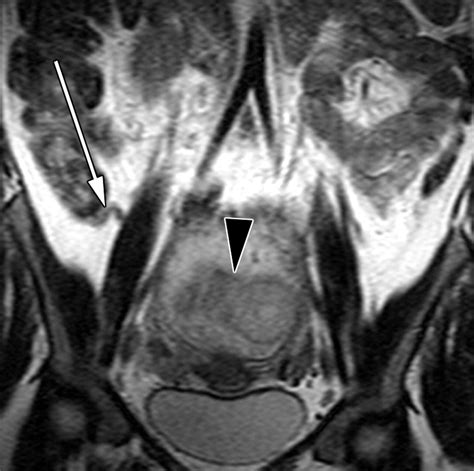

• Fetal Anomalies: MRI can provide detailed images of the fetus, helping to detect congenital anomalies that may not be visible on ultrasound. This information is crucial for planning prenatal care and preparing for potential complications at birth.

• Placental Abnormalities: MRI can help identify placental abnormalities, such as placenta previa or placental abruption, which can pose significant risks to both the mother and the fetus.

• Maternal Conditions: MRI is also used to evaluate maternal conditions that may affect pregnancy, such as pelvic masses, uterine fibroids, or spinal disorders. By providing detailed images of these structures, MRI can help guide treatment decisions and improve outcomes.